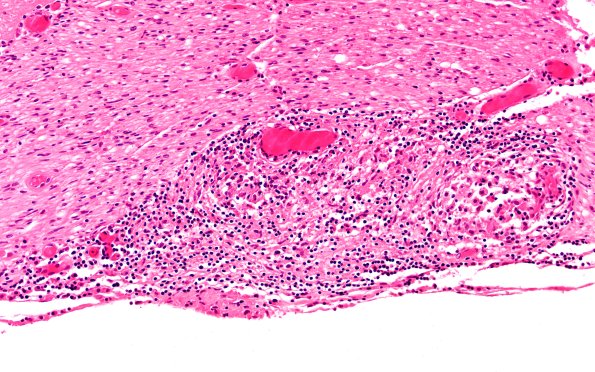

Washington University Experience | PERIPHERAL NEUROPATHY | 9A SARCOID | 4B3 Neurosarcoid NP (Case 4) H&E 20X

Higher magnifications of the root identified by an arrow in image #B1. The granulomas are accompanied by a lymphocytic infiltrate. (H&E)